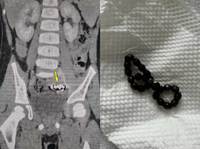

¸»ÃÊ½Å°æ ¸¶ºñ¸¦ À¯¹ßÇÏ´Â ¡®½Å°æ³» °áÀýÁ¾(intraneural ganglion cyst)ÀÇ º¹ÀâÇÑ ¹ß»ý ±âÀüÀÌ È®ÀεƴÙ.½Å°æ³» °áÀýÁ¾Àº °üÀý ³»ºÎÀÇ È°¾×ÀÌ ½Å°æ Áö¹è ºÐÁö¸¦ Ÿ°í ¿ª·ùÇØ ½Å°æ Áٱ⠳»ºÎ¿¡ ³¶Á¾À» Çü¼ºÇÏ´Â ÁúȯÀÌ´Ù. ¿øÀÎÀÌ ºÒºÐ¸íÇØ ¼ö¼ú ÈÄ¿¡µµ Àç¹ßÀÌ Àæ°í ¿µ±¸Àû..